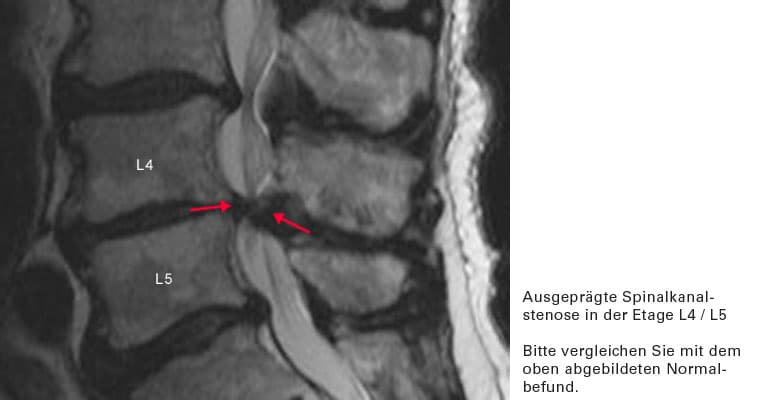

Es liegt eine krankhafte Verengung des Wirbelkanales vor (Stenose des Spinalkanales). Diese tritt in der Regel erst in höherem Alter auf. Sie wird verursacht durch:

• eine sich breitbasig vorwölbende Bandscheibe

• eine Verdickung des Bandapparates, welcher den Wirbelkanal auskleidet

• Verschleiß von Wirbeln und Wirbelgelenken, die knöcherne Anbauten entwickeln, welche in den Wirbelkanal hineinragen